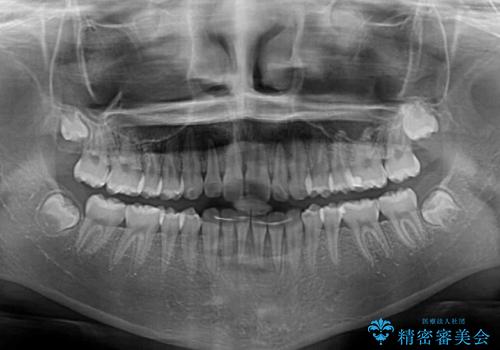

上下ともに少し捻れが残っていたため、治療の継続を提案しましたが、本人も親御さんも満足とのことで、治療を終えました。

捻れの改善により突出感も改善されました。